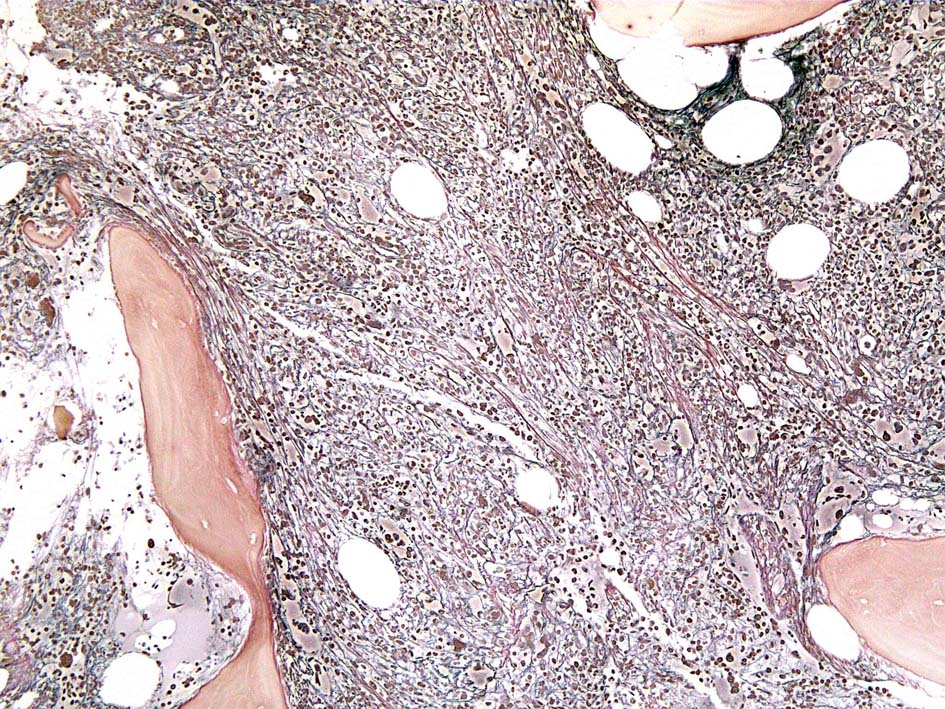

塗銀染色

CD42b染色

黒染する弾性線維の増生のほか, 赤く染まる膠原線維の増生が確認される. MF-2 fibrosis. 鍍銀染色の核染色をすると膠原線維の赤染がわからなくなるので行わない.